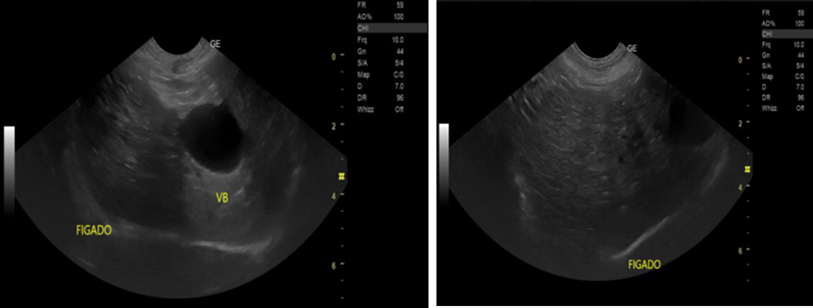

Xanthogranulomatous Pyelonephritis: An Uncommon Form of Pyelonephritis Highlighted in a Case Report

Danielle Malavazi Oliveira; Bárbara Sthefany de Paula Lacerda; Matheus Compart Hemerly, Maria Isabel Lima dos Santos, Weverton Machado Luchi